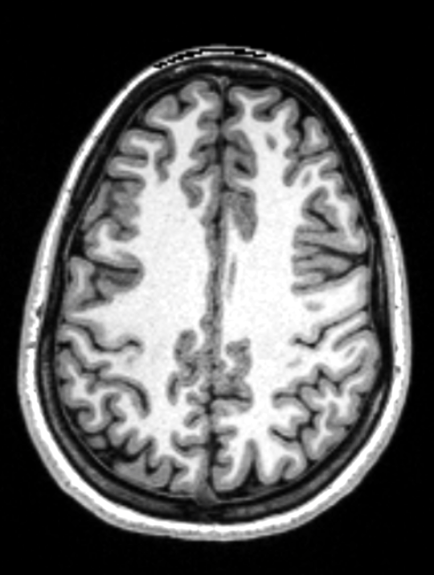

Brain Morphometry

??

Tables.

Klein A, Ghosh SS, Bao FS, Giard J, Häme Y, Stavsky E, Lee N, Rossa B, Reuter M, Neto EC, Keshavan A. Mindboggling morphometry of human brains. PLoS computational biology. 2017 Feb 23;13(2):e1005350.

Keshavan, Anisha, Arno Klein, and Ben Cipollini. "Interactive online brain shape visualization." Research Ideas and Outcomes 3 (2017): e12358.